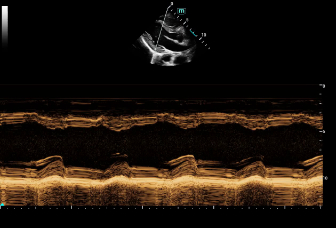

Consona presenta soluzioni nuove e concrete, che aiutano a effettuare diagnosi efficaci con semplicitĂ , rivolgendosi a un'ampia platea di pazienti. La serie mette a disposizione strumenti estremamente avanzati per rimanere all'avanguardia nella diagnosi cardiovascolare.

Galleria di immagini